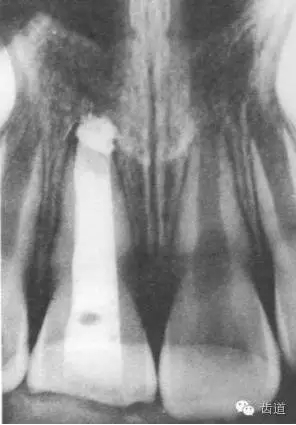

術(shù)后一個月

術(shù)后當(dāng)天

術(shù)后11個月

術(shù)后五個月